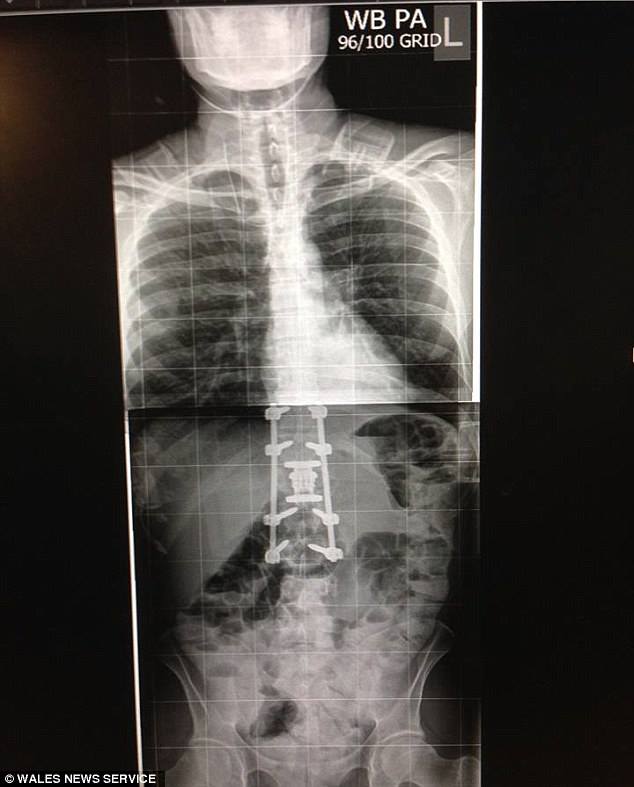

بەهۆی كەوتنەكەیەوە، پێنج بڕبڕەی پشتی ناوبراو شكاو سەری برینداربوو، بە تەواوی توانای جوڵاندنی قاچەكانی بۆ ماوەیەكی كاتیی لەدەستدا.

پزیشكەكان بە ناوبراو و ڕەیچڵ-ی هاوسەرییان ڕاگەیاند كە ئەگەر هەیە ناوبراو هەرگیز دوبارە توانای بەكارهێنانی قاچەكانی نەمێنێتو تا كۆتایی تەمەنی لەسەر كورسی جوڵاو بەسەربەرێت. بەڵام بەشێوەیەكی زۆر سەرسوڕهێنەر و پاش تێپەڕینی 19 رۆژ دەستیكردەوە بە جوڵاندنی قاچەكانی.